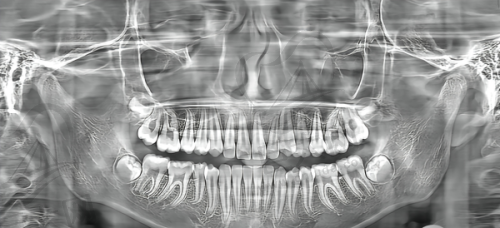

数字化种植牙是宣城大医口腔的特色项目之一。其中,数字化导板种植牙相比传统的种植牙有诸多优势。传统种植牙在手术过程中可能存在一定的不确定性,而数字化导板种植牙运用了数字导板技术植入植体。这种技术可以避开神经血管,增加了手术的成功几率和植体的存活能力。对于那些需要种植牙的患者来说,这无疑是一个更安心、更可靠的选择。想象一下,在进行种植牙手术时,能够精细地避开神经血管,大大降低手术风险,术后植体的存活能力也更高,这对于修复口腔功能和美观都有着重要的意义。